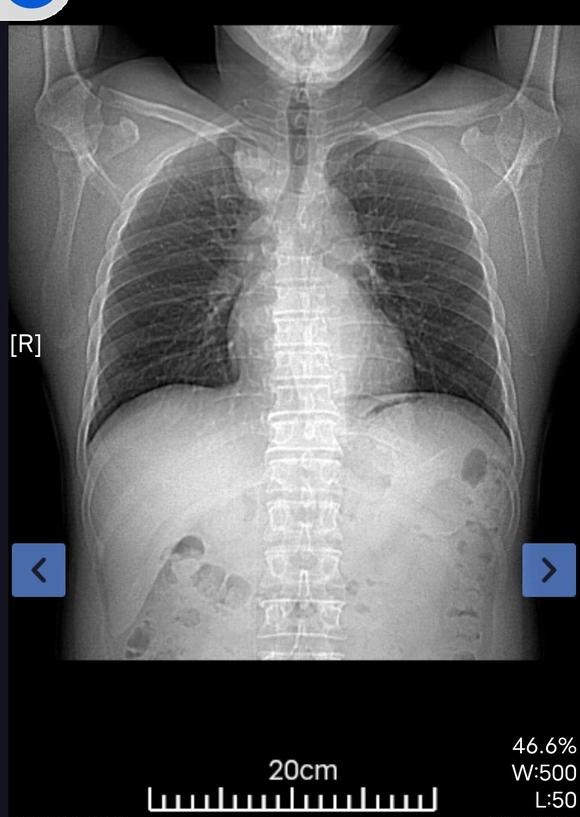

北港永下 02021-12-21 患者家属我父亲体检时发现有肿块。到人民医院检查结果显示食管囊肿或支气管囊肿本来医生说不是很大的手术。几天前做了增强ct。又说有可...